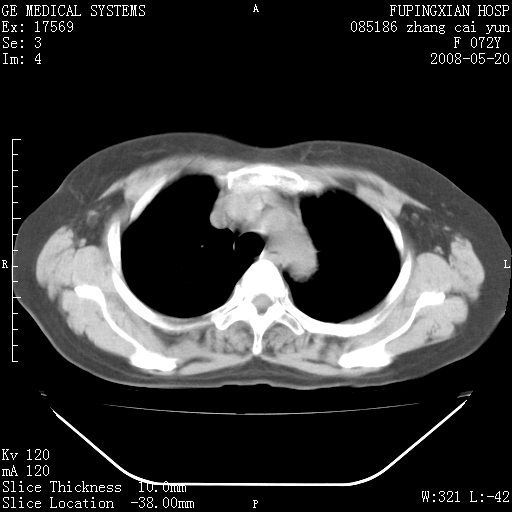

标题: CT13542:发热,咳嗽数日,经抗菌素治疗好转,请大家看排除 [打印本页]

标题: CT13542:发热,咳嗽数日,经抗菌素治疗好转,请大家看排除

上叶支气管略变窄并通畅,内壁光滑。考虑:单纯阻塞性肺炎!

右上叶支气管走行自然,未见明显管壁增厚等征像,另左主支气管起始部可见异常腔道向左侧延展左肺动脉干后方,与左下叶支气管相通,为左下叶支气管变异?

有节段性阻塞性肺炎与不张,近段支气管狭窄,周围散在肿大淋巴结影,以周围型肺癌可能性大,建议纤支镜检查。

右肺上叶实变影,内见支气管充气征,右上叶支气管通畅,肺门区未见软组织密度影,抗炎治疗有效,考虑炎症,建议继续抗炎治疗复查。

右上肺实变,间内有支气管充气征,考虑炎症,建议抗炎后复查